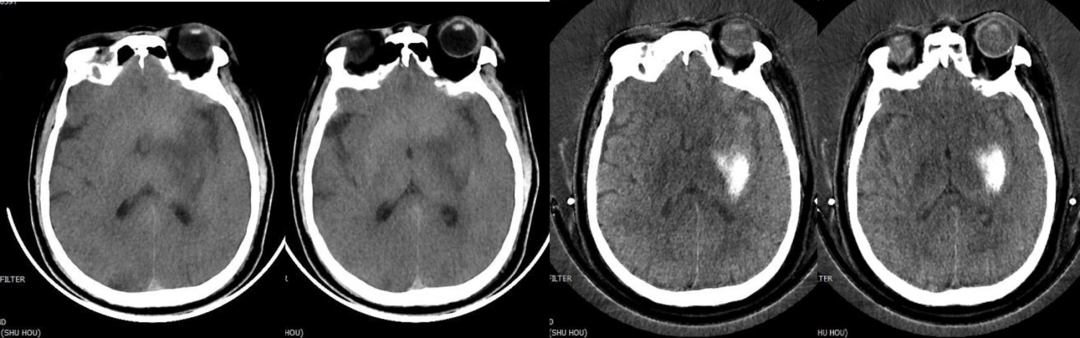

5.去金屬偽影:能譜CT單能量成像結(jié)合MAR技術(shù)可在顱腦成像、顱內(nèi)動(dòng)脈瘤夾閉術(shù)后及骨關(guān)節(jié)金屬植入術(shù)后復(fù)查中獲得較好成像效果。